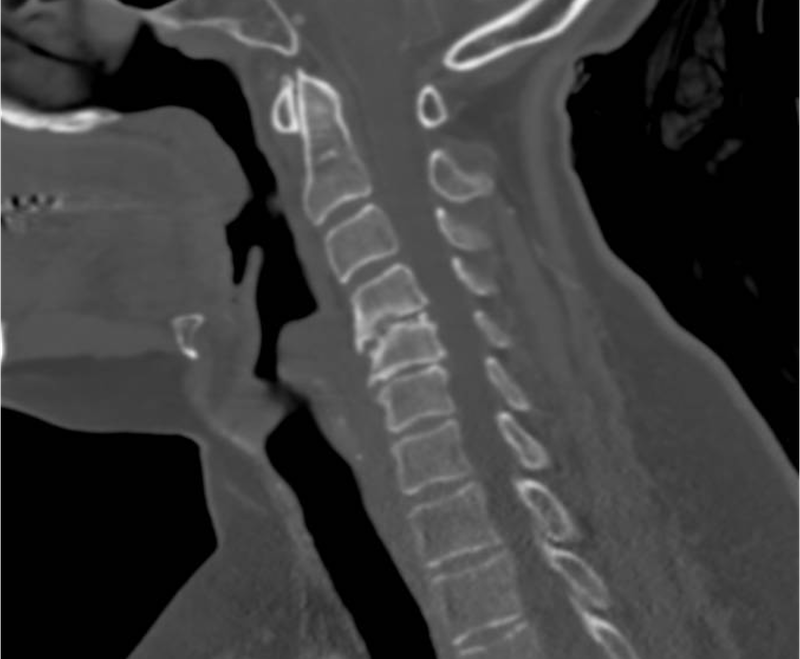

CT scan image of a human neck showing cervical vertebrae and surrounding tissues.

• Not always. Imaging is used when symptoms persist or worsen.

• X-rays may show signs of disc degeneration, including disc height loss and bone spurs.

• Not always. Symptoms do not always match imaging findings.